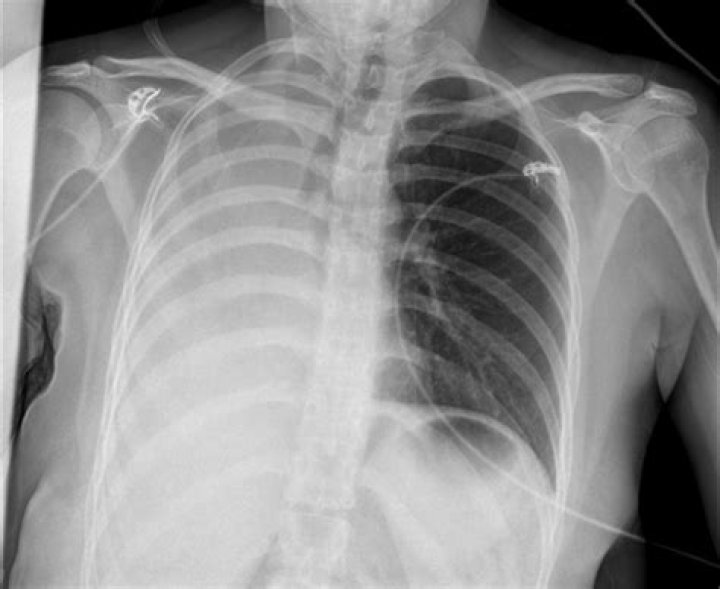

What happens when one lung collapses?

A collapsed lung occurs when air escapes from the lung. The air then fills the space outside of the lung between the lung and chest wall. This buildup of air puts pressure on the lung, so it cannot expand as much as it normally does when you take a breath. The medical name of this condition is pneumothorax.

Some possible complications of these procedures may include, but are not limited to, the following: Pneumothorax is when air becomes trapped in the pleural space causing the lung to collapse. Bleeding in the lung. Infection.

Pneumothorax is the most common complication of transthoracic lung biopsy (4). A patient with stable pneumothorax may be treated conservatively without chest tube insertion. If pneumothorax is large (greater than 30% of hemithorax), is rapidly expanding, or is causing symptoms, chest tube insertion is warranted.

Pneumothorax. The most common complication of chest biopsy is development of a pneumothorax. The largest retrospective series placed the incidence of pneumothorax at 20.5% and the incidence of pneumothorax requiring chest drainage at 3.1%.